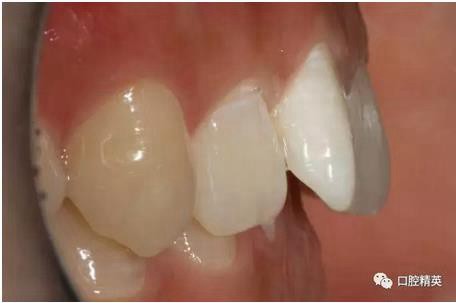

口內(nèi)正側(cè)位及切端特寫

從側(cè)位照可看出遠中切角略有回收